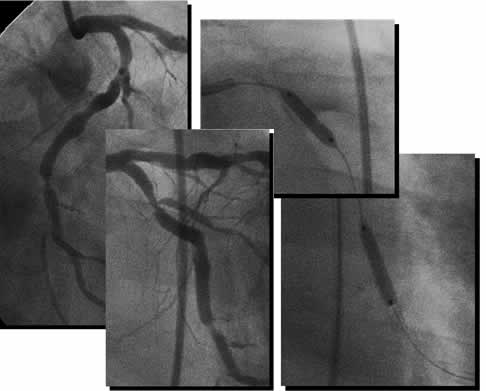

Case F-3

| Diagnosis: OMI (A&I), DVD

Present Illness: '94 AMI (I) '97 AMI (A) '01.3.16 CAG: #8 90%, #9 90%, #13 99% POBA for #8 and stenting for #13 '01.9~ recurrent EA |

| Final CAG Findings:'01.9.18 LVG: asynergy (A&I), EF: 44% CAG: #9 90%, #10 90%, #11 75%, #13 proximal 75%, #13 distal 90% |

Control

Cutting Balloon

3.0mm@8atm |